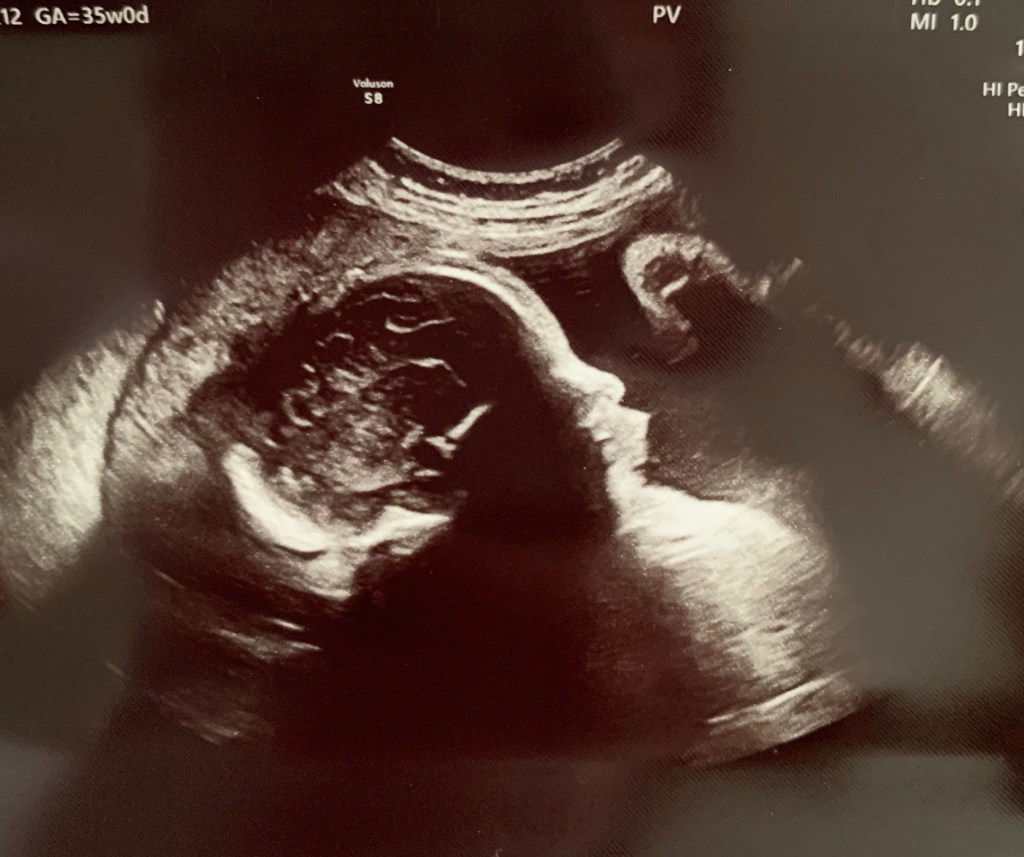

Face profile

The 36 week appointment was the next growth scan during the ultrasound. This scan estimated baby’s weight at 7lbs 7oz which is the 90th percentile. While this is large, the main concern was that baby’s abdomen was measuring large rather than concern for their overall size. With a larger abdomen there is a higher risk of baby’s shoulder being dislocated during delivery or just getting stuck in the birth canal in general. Baby was also still breech, but not surprising as he or she has been head up most of the pregnancy and I had seen that on each week’s ultrasound. The 36 week appointment was also a cervical check where I was not dilated at all yet and a swab to test for strep B (which came back negative). If I had tested positive for strep B, I may have needed some antibiotics at the time of delivery to help prevent passing it along to the baby. After this appointment is when we started discussing with my care team what would be the best delivery options and when. More on this towards the end…